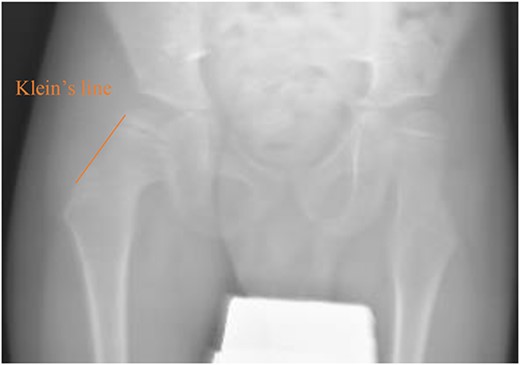

A 5-year-old independent ambulatory Middle Eastern boy with CP who was born preterm and developed grade III intraventricular haemorrhage and periventricular leucomalacia and was on AEDs, including valproic acid (VPA) and levetiracetam (LEV), for >3 years and was controlled over the last year (no history of seizure attack) presented to the emergency room (ER) with right hip pain and inability to bear weight for 4 weeks; the patient had no history of fever or trauma. Physical examination shows a thin, the weight is 12 kg, the height is 101 cm, vital signs within the normal range, tenderness over the right hip, and external rotation of the right hip, with restricted hip mobility. A radiological study was performed ~3 months before the patient presented to the ER for follow-up examination of a left hip coxa valgus deformity with no apparent abnormalities in the right hip (Fig. 1). Initial imaging studies conducted in the ER showed an anterior–posterior view of the pelvic radiograph, revealing Klein’s line [13] not intersecting the capital femoral epiphysis (Fig. 2), and frog-leg lateral view radiograph of the right hip (Fig. 3) confirmed SCFE and Southwick’s slip angle [13] of ~50° (moderate). Laboratory findings were clear for endocrine and renal diseases or infection, except for low vitamin D (total 25-OH Vitamin D: 43.4 nmol/L), suggesting vitamin D insufficiency. The diagnosis was confirmed with clinical and radiological studies as right-sided unstable SCFE requiring surgery. Surgical intervention was performed with percutaneous in situ fixation using a single fully threaded 4.5-mm cannulated screw (Fig. 4). Postsurgical rehabilitation included non-weight-bearing right lower extremities for 6 weeks. Regular follow-up with serial radiology studies showed stable fixation with no migration of screw or further slippage at 6 weeks (Fig. 5) and 3 (Fig. 6), 15 (Fig. 7), and 36 months (Fig. 8). During follow-up, a painless range of motion in the right hip was observed, with full weight-bearing and resumption of his usual activities with no complaints.

Pelvic frog-leg lateral view radiograph showing Southwick’s slip angle 50° in the right hip.